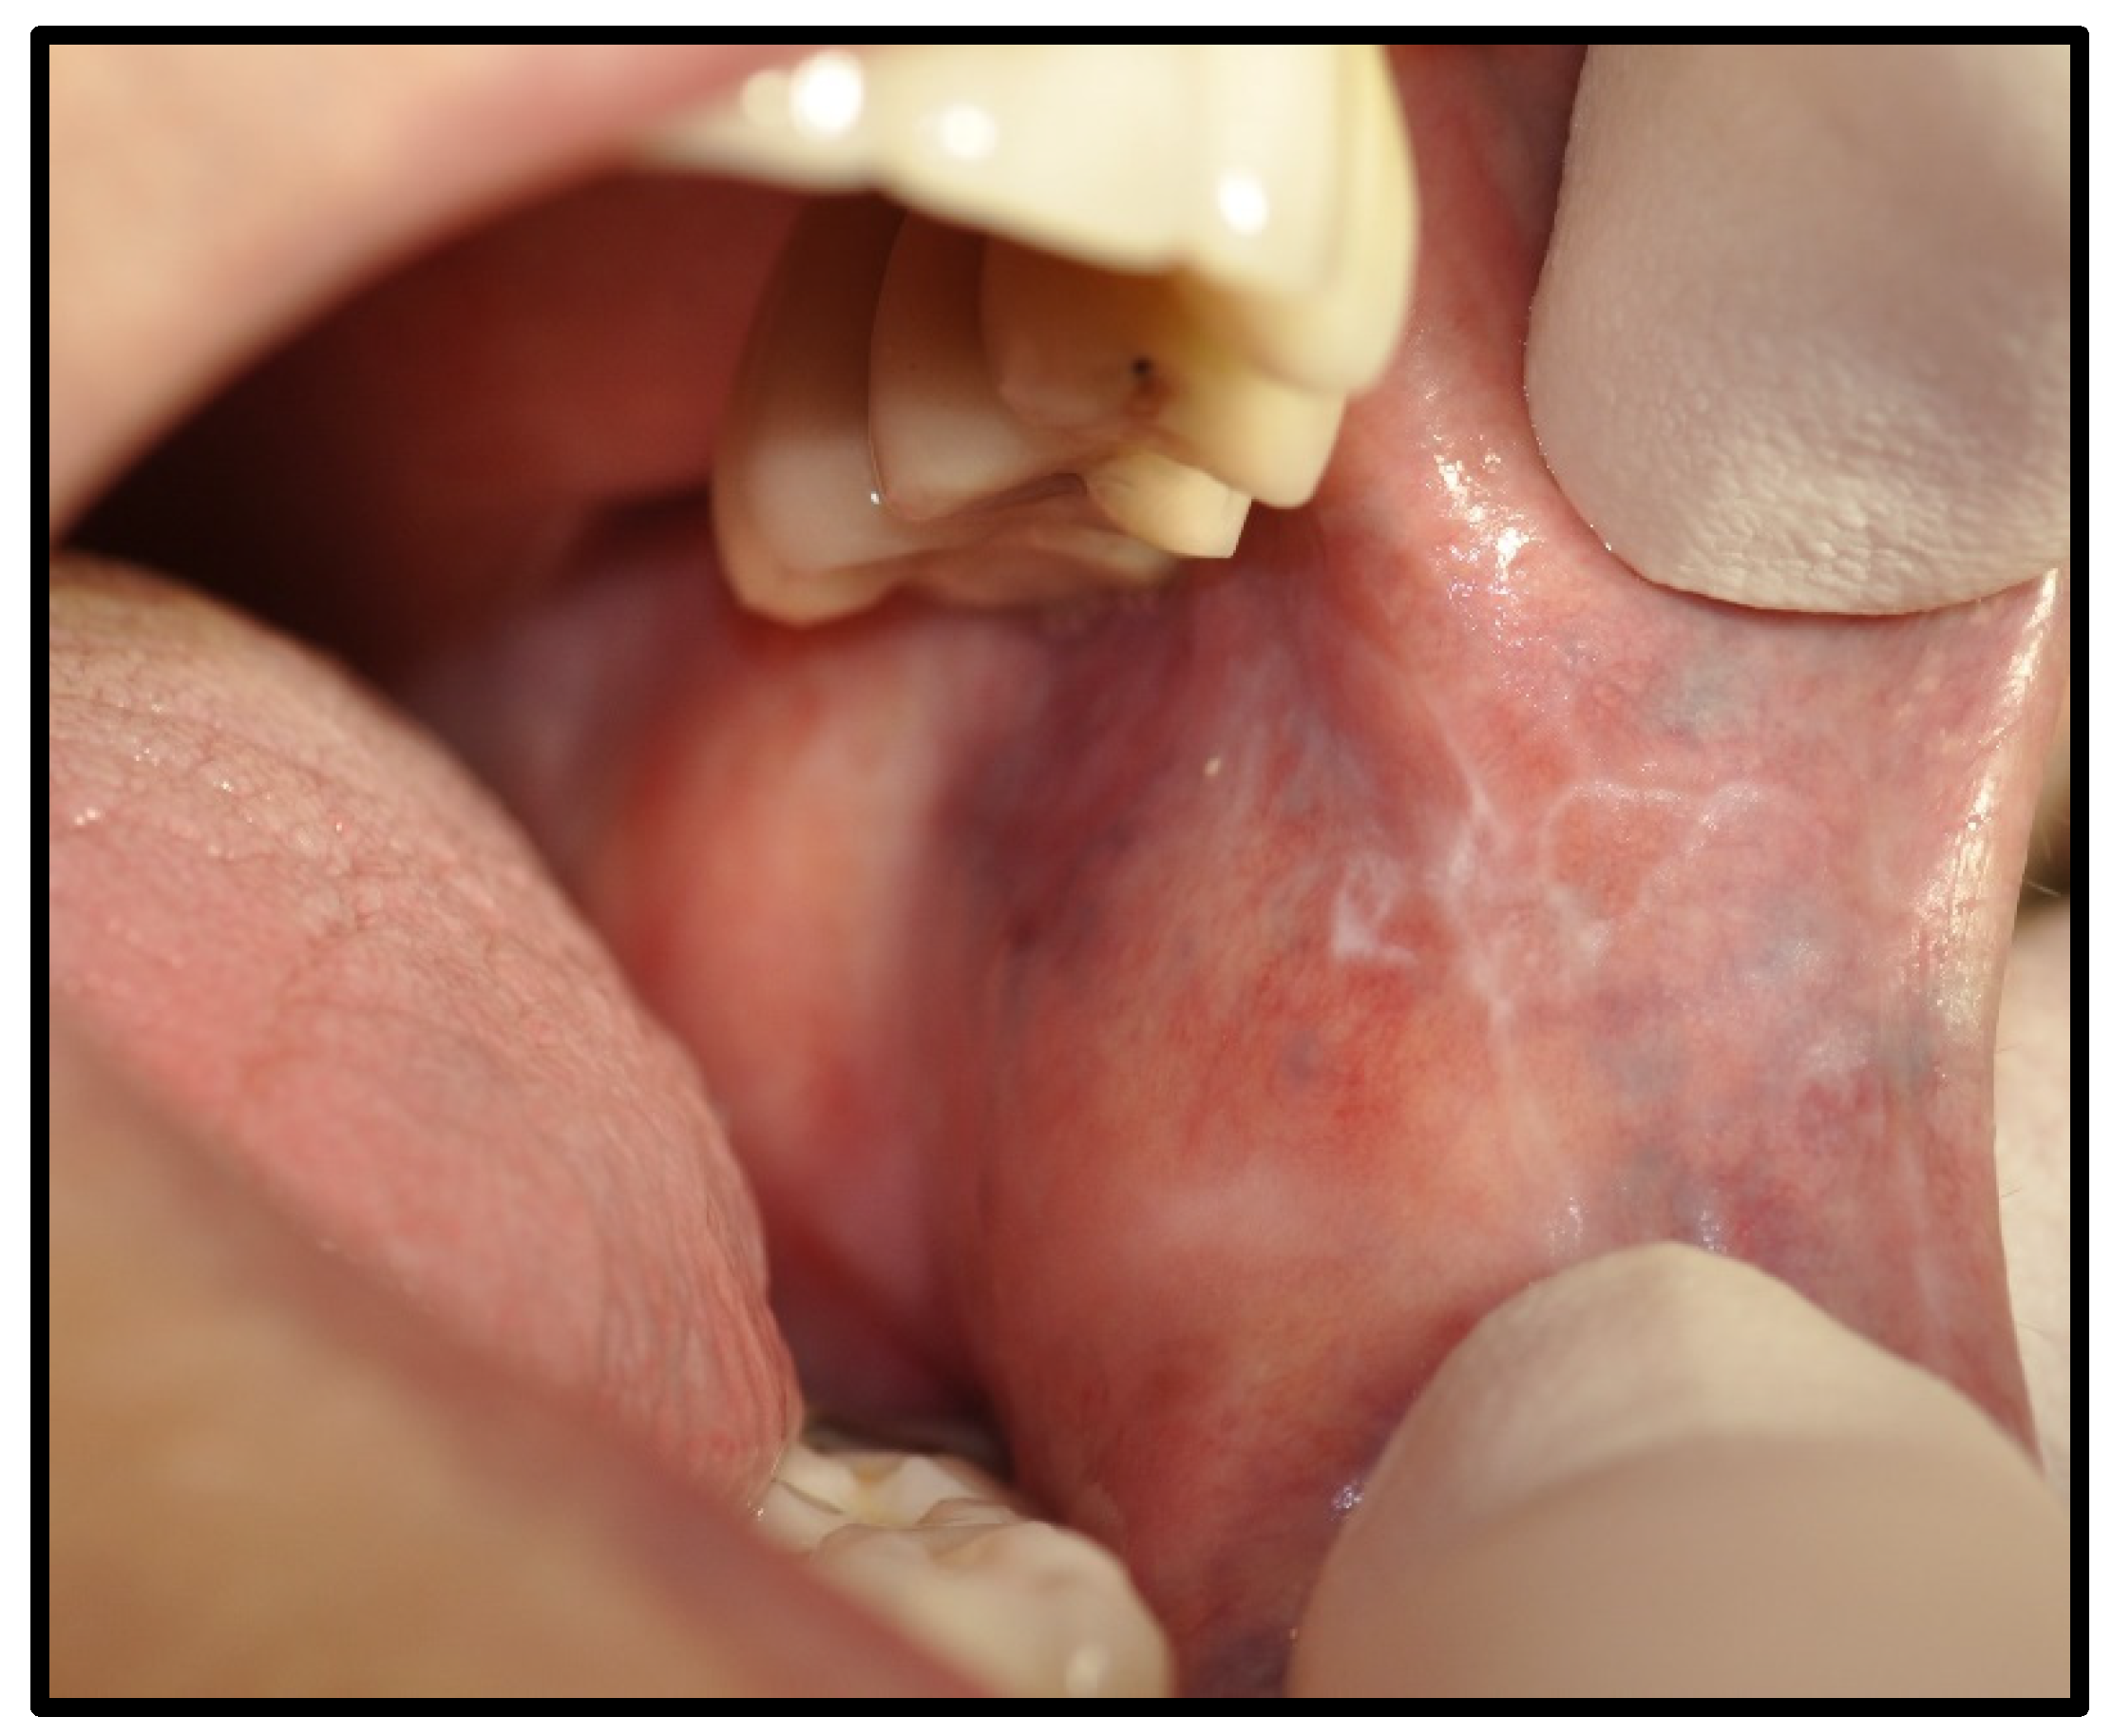

| OLP/lichenoid reaction (3 were exacerbations of previous autoimmune disease) | 12 | 50.00 | |